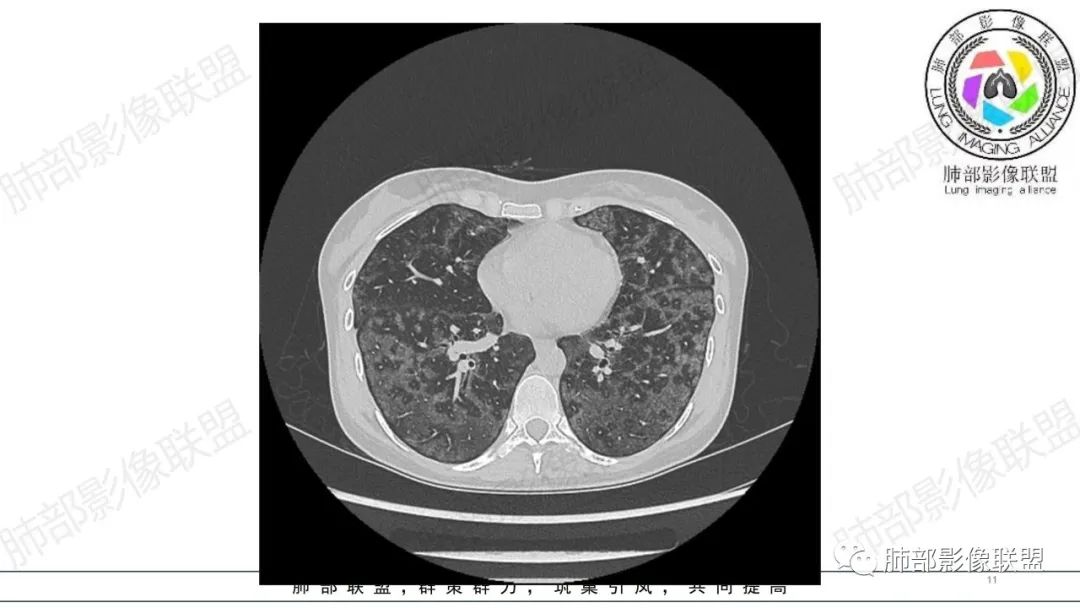

影像资料

34岁女性患者,“哮喘”病史30年,近期有可疑刺激性气体吸入史;因乏力半年,咳嗽、憋气、发热4天就诊;6.1CT提示双肺广泛毛玻璃影及粟粒样结节,胸膜下闲置及血管周闲置,可见树丫征,部分小叶间隔增厚。考虑:1.过敏性肺泡炎,有可疑刺激气体接触史,胸膜下闲置,广泛毛玻璃影,地图样分布,粟粒结节边界模糊,支持过敏性肺泡炎,但糖皮激素治疗效果不佳,且动态复查血常规血红蛋白进行性降低,过敏性肺泡炎 不符合;2.肺含铁血黄素沉积症:患者30“哮喘”病史,可能为肺含铁症状,肺部CT提示双肺弥漫毛玻璃影及粟粒结节影,中下肺明显,肺底部分小叶间隔增厚,近期咳嗽、憋气、发热,血常规血红蛋白进行性下降,考虑肺含铁急性期症状,但临床无咯血症状,肺含铁不典型。综合考虑:肺含铁血黄素沉积症>过敏性肺泡炎。

年轻女性 ,急性喘息发热,肺部影像弥漫磨玻璃密度,部分细小腺泡结节,胸膜下黑线显示,短期复查,病变密度增高,下肺明显,血管周围肺组织累及较少、且逐渐成小叶间隔分布。考虑弥漫肺泡内病变,并经淋巴道转移,下肺比上肺明显,多为免疫细胞功能下肺较强。1.过敏性肺泡炎,有相关病史,三层密度特点、头尾测分布,符合。2 肺泡微石症,多有钙化,且缓慢起病,病程不太符合,放待排。3 吸入相关肺损伤,有病史,疾病演变过程也符合渗出-肉芽肿改变,建议详细询问病史。4 感染性病变,结核?病变气道分布为主,如此弥漫且没有树丫不符合。5.巨细胞病毒,可以磨玻璃 结节 改变,没有免疫缺陷病史。最后考虑吸入所致 1过敏性肺泡炎、吸入性肺损伤 鉴别肺泡微石症。

肺内气腔磨玻璃结节,肝脾肿大,治疗后间质改变,弥漫大B可能